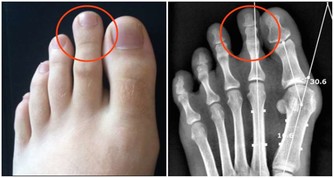

具體來說,大腸癌通常有以下症狀:便秘和腹瀉反復發生、有血便和便血、糞便很細、排便不爽、總感覺排便沒有排完全、腹部有腫塊、腹痛、有貧血症狀等等。